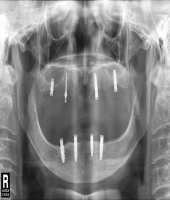

| ● 진료과목 : [임플란트] 임플란트 지지 틀니

| ● 내용 : 상악 임플란트 지지 틀니와 하악 고정식 보철의 만남. |